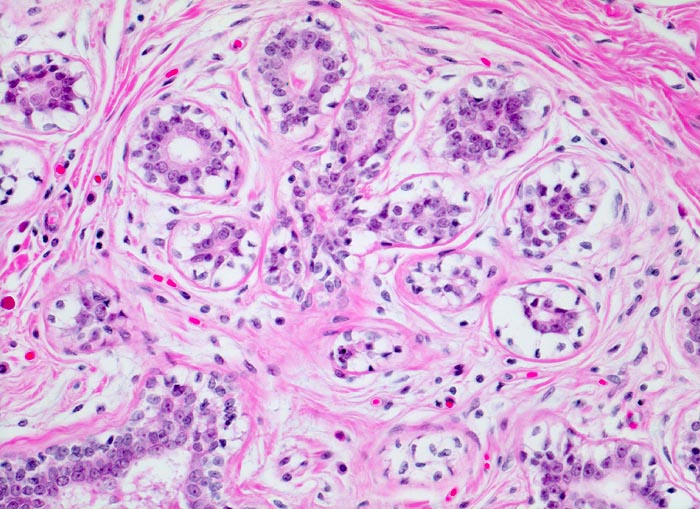

Die terminale duktulolobuläre Einheit der Mamma umfasst einen intralobulären Ausführgang und zu einem Läppchen angeordnete Alveolen. Alveolen und Ausführgang werden vom gleichen zweischichtigen Epithel ausgekleidet. Das intralobuläre kollagenfasrige Gewebe ist etwas lockerer als das extralobuläre.